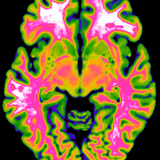

Biological Psychology & Imaging

Claus Lamm, University of Vienna, Faculty of Psychology, together with Rupert Lanzenberger, Medical University of Vienna, Department of Psychiatry and Psychotherapy: Multimodal Neuroimaging in Clinical Neurosciences: Assessment of neurobiological markers for psychiatric disorders.